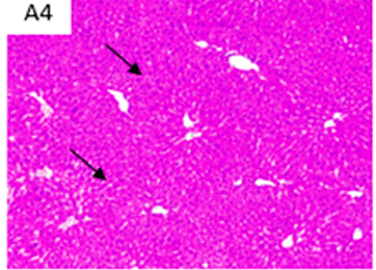

Fotografías a cortes histológicos de hígado, después de 12 semanas, parte de ensayo preclínico: CD: dieta control; HFD: dieta alta en grasa; A1: dieta alta en grasa + concentrado Omega-3 pescado; y A4: dieta alta en grasa + lípidos terapéuticos Nutri-Omics. Flechas muestran los distintos niveles de gravedad de los focos de esteatosis macro y micro vesicular después de ser sometidos a una dieta alta en grasa.